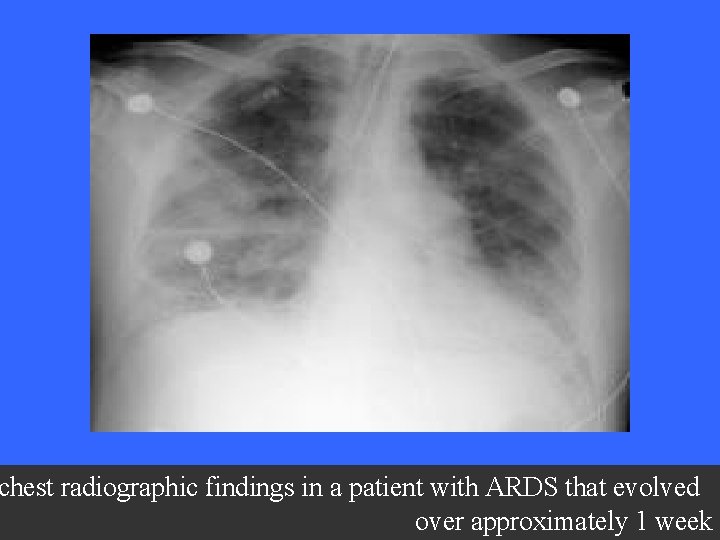

CXR Chest radiographic findings are non-specific and resemble those of typical pulmonary edema or pulmonary hemorrhage. There are diffuse bilateral coalescent opacities (the only radiological criterion defined by the Consensus Conference). The time course of ARDS may help in differentiating it from typical pulmonary edema. Chest x-ray features usually develop 12 -24 hours after initial lung insult as a result of proteinaceous interstitial edema. Within one week, alveolar pulmonary edema (hyaline membrane) occurs due to type 1 pneumocyte damage. In contrast to cardiogenic pulmonary edema, which clears in response to diuretic therapy, ARDS persists for days to weeks.

The patient had been in respiratory failure for 1 week with the diagnosis of ARDS. .

chest radiographic findings in a patient with ARDS that evolved over approximately 1 week